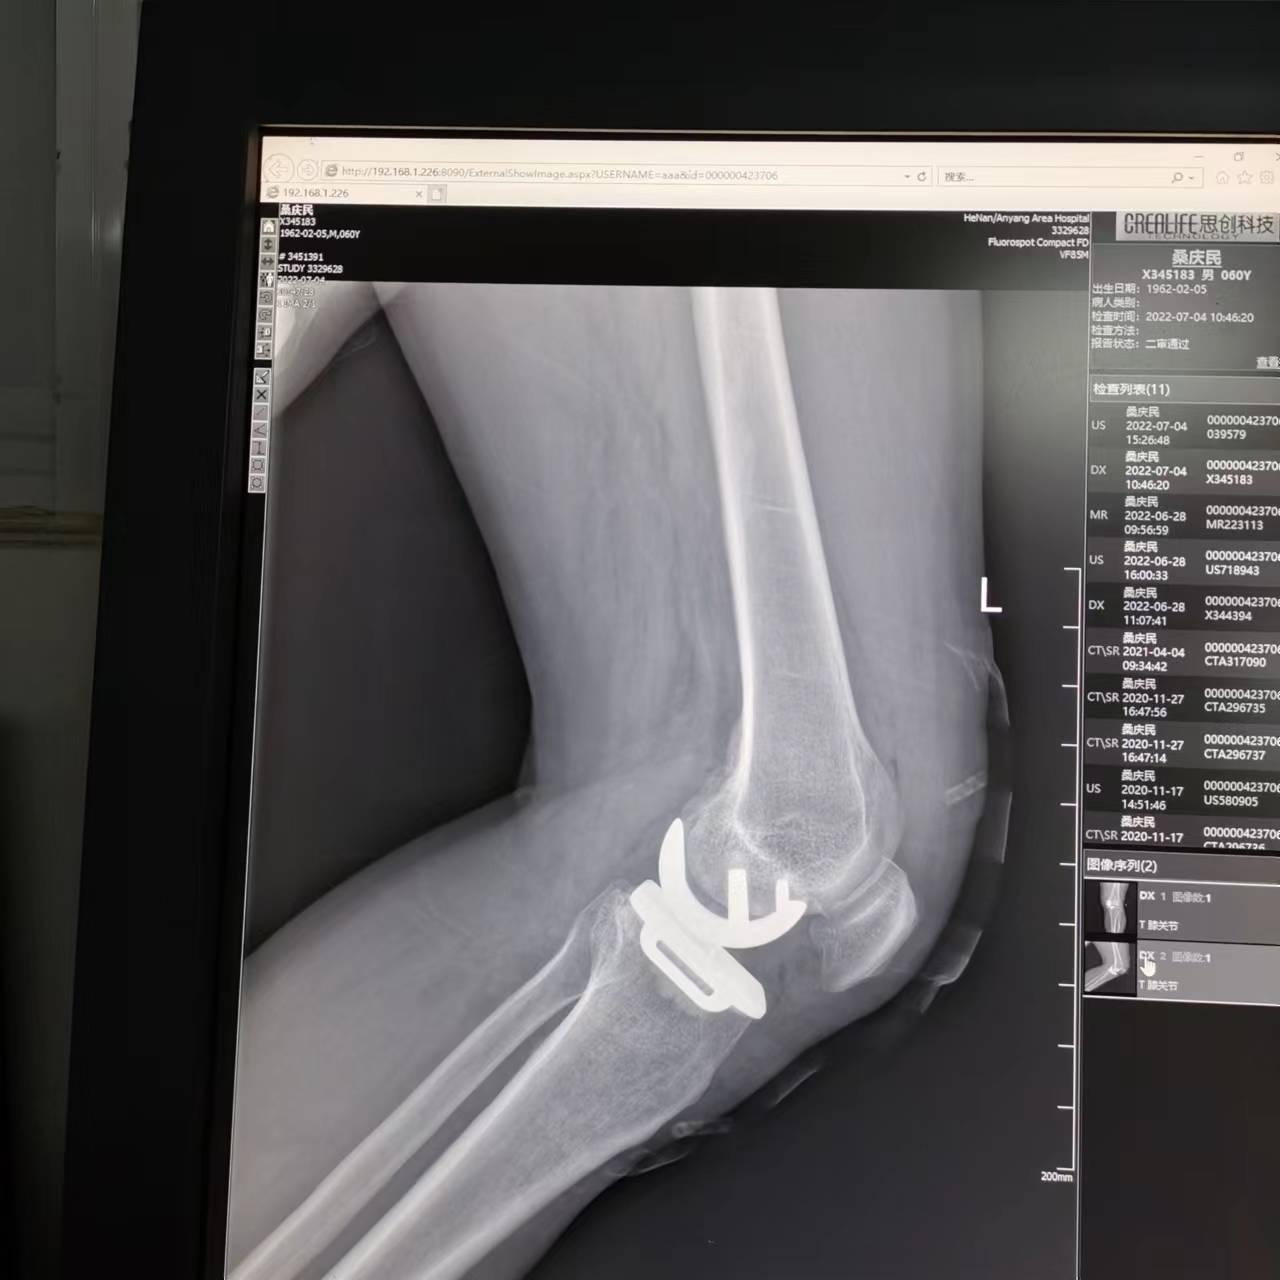

C、关节假体不同:

2、全膝置换:全膝置换是针对整个膝关节进行置换,包括胫骨平台、股骨远端部位等,所以假体相对较大,患者术后关节活动的自如度略小。